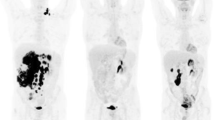

On a per-lesion basis, pooled SUVmax, SUVmean, ADCmin and ADCmean values from all lymphoma subtypes differed significantly between baseline and FU-1 (−46.8%, −33.3%, +20.3% and +14%, respectively; P < 0.001), between baseline and FU-2 (−65.1%, −49%, +50.7% and +32.4%, respectively; P < 0.001), and between FU-1 and FU-2 (−34.5%, −23.5%, +24.2% and +15.2%, respectively; P < 0.001). MTV also differed significantly between baseline and FU-1 (−46%; P = 0.002), and between baseline and FU-2 (−61.1%; P < 0.001), but not between FU-1 and FU-2 (−28%; P = 0.79) whereas VOL differed significantly only between baseline and FU-2 (−24.2%; P < 0.001), and not between baseline and FU-1 (−12.8%; P = 0.079), or between FU-1 and FU-2 (−13.1%; P = 0.154; Table 2, Figs. 1 and 2).

A 68-year-old woman with DLBCL of the left adrenal gland (blue arrows). The lymphoma shows intense glucose metabolism (high [18F]FDG uptake; high SUVs) at baseline on the axial fused [18F]FDG PET/MR image, and a clear diffusion restriction on the DWI image (high signal) and the ADC map (low signal). The PET/MR image at 48–72 h after treatment initiation (R-CHOP) shows an almost complete reduction in [18F]FDG uptake (reduced glucose metabolism) and a clear increase in tissue diffusivity (increased ADC, indicating reduced cell density) at this time-point. The PET/MR image at 1 week after treatment initiation shows an additional moderate decrease in lesion size relative to the baseline image

On a per-patient basis, pooled SUVmax, SUVmean, ADCmin and ADCmean values from all lymphoma subtypes differed significantly between baseline and FU-1 (−54.9%, −41.7%, +27.8% and +17.8%, respectively; P < 0.001), and between baseline and FU-2 (−70.7%, −55.9%, +58% and +34.4%, respectively; P < 0.001). SUVmean, ADCmin and ADCmean, but not SUVmax, differed significantly between FU-1 and FU-2 (−24.6%, +23.6%, +14.1% and −35%, respectively; P = 0.015, P < 0.001, P < 0.001 and P = 0.094). MTV also differed significantly between baseline and FU-1 (−42.9%; P = 0.01), and between baseline and FU-2 (−53.9%; P = 0.001), but not between FU-1 and FU-2 (−19.2%; P = 1.0), whereas VOL differed significantly only between baseline and FU-2 (−18.7%; P = 0.002), and not between baseline and FU-1 (−12%; P = 0.069), or between FU-1 and FU-2 (−7.6%; P = 0.62). Line graphs revealed major differences in treatment response between individual patients, and even between patients with the same lymphoma subtype and treatment regimen (Online Resource 1).